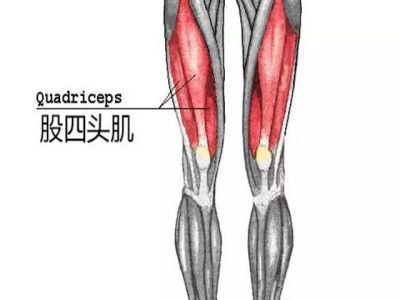

股四头肌腱损伤

在我们手所能触摸到的膝盖的那块“圆骨头”(髌骨)之上,是人体最大的肌肉群,股四头肌的肌腱所在,股四头肌腱像一条宽胶带一样黏在髌骨上,股四头肌收缩时使膝伸直,人类就是利用这些肌肉行走和奔跑的。所以,当膝关节上方出现疼痛时,很有可能是股四头肌腱出现了问题,比如严重的外伤、运动不当、运动场地温度过低湿度过大等原因引起。一般股四头肌腱损伤的患者在跑步启动加速时大腿伸直那一刻会感觉到大腿突然疼痛,轻度的仅仅是局部有血肿或轻度的肿胀,按压髌骨上端会有疼痛,抬小腿困难,严重的会导致膝关节弯曲困难,疼痛,尤其是在伸小腿屈大腿时会疼痛特别明显。